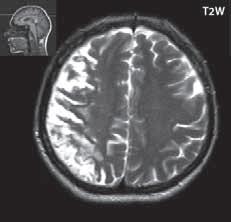

Obr. I.1.2a Paralelní postavení postranních komor, kolpocefalie, ageneze corpus callosum

Obr. I.1.2b Ageneze corpus callosum

Při agenezi corpus callosum CT i MR zobrazí paralelní průběh postranních mozkových komor (oproti fyziologickému

konvergentnímu průběhu) a jejich oddálení, časté rozšíření okcipitálních rohů – colpocefalie, někdy středočárový lipom, cystu. Koronální řezy ukážou rozšíření frontálních rohů postranních komor, III. komora je situována vysoko mezi postranní komory, tvoří jakoby trojzubec, který někteří autoři přirovnávají k přilbě Vikinga. Není patrné septum pellucidum. Častá je přítomnost středočárového lipomu nebo cysty.

Na vnitřní straně postranních komor pozorujeme v T2W obrazu poněkud tmavší strukturu než okolní myelinizovaná vlákna (naopak v T1W obrazu zvýšený signál), Probstovy provazce, axony, které za fyziologických okolností přecházejí přes corpus callosum do kontralaterální hemisféry.

Sagitální řezy nám přinášejí nejvíce informací o corpus callosum. Pozorujeme radiální průběh mozkových sulků ke stropu III. komory na vnitřní straně mozkových hemisfér a naopak nezobrazíme gyrus cinguli. Při parciální agenezi je postiženo především splenium.